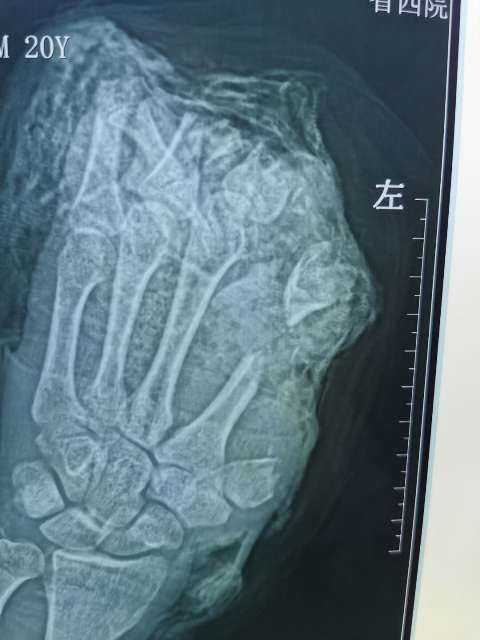

10月6日,20岁的小伙在工厂干活时左手不慎被切割机致左手拇指、示、中、环指完全离断;左小指开放伤伴肌腱神经血管离断;大鱼际皮肤软组织、环指中末节部分缺损、第一掌骨、第二掌骨部分缺损,鲜血直流。被工友慕名紧急送往日韩无码

经过骨二科和手术室医务人员历时10小时,彻底清除污染失活组织及伤口内大量铁屑异物、逐步固定指骨、缝合肌腱,显微下再次清创后吻合离断神经;术中见离断动脉大部分挫伤严重无法吻合就近利用手背侧静脉,移植搭桥吻合缺损动脉完成4指离断一期急诊再植,术后经补液输血,支持,抗感染,抗凝,抗痉挛,扩血管等“三抗一扩”对症治疗。目前患者再植指体成活良好,已经基本度过危险期,保住了患者的四个手指。